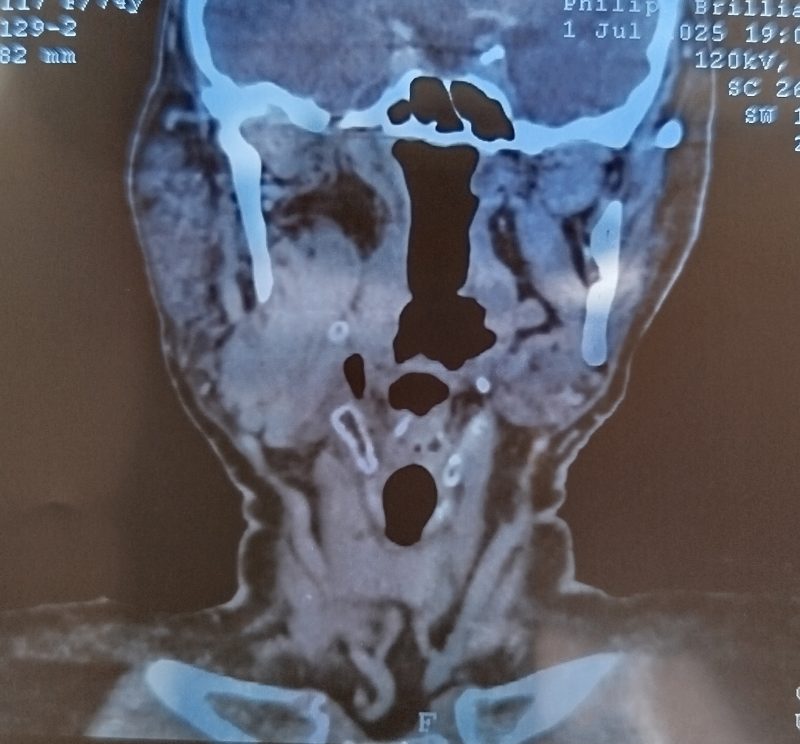

Пациент К. 1950 гр. Поступил в ООГШ 26.08.2025 с жалобами на новообразование шеи справа. Считает себя больным около 6 лет. В поликлинику по месту жительства обратился в июне 2025г. В рамках обследования было проведено МРТ шеи: В проекции каротидного и заднего шейного пространства визуализируется объёмное образование с четкими бугристыми контурами, размерами до 45х36х49 мм, с признаками интенсивного равномерного накопления контрастного вещества, с признаками ограничения диффузии. Внутренняя сонная артерия справа огибает образование, яремная вена на уровне образования достоверно не прослеживается- вероятно вовлечена в процесс. МР-картина объемного образования сосудистого и заднего шейного пространств шеи справа с вовлечением яремной вены? Направлен в БУЗ ВО «ВОНКОЦ» для уточнения диагноза. В поликлинике БУЗ ВО ВОНКОЦ выполнена ТИАБ (тонкоигольная аспирационная биопсия) образования шеи справа. Цитологическая картина — клетки атипии, дистрофии. Госпитализирован в отделение ООГШ для проведения хирургического лечения с целью установки морфологической верификации.

27.08.2025 было проведено удаление опухоли мягких тканей шеи справа. При ревизии выявлена опухоль мягких тканей 5х6 см, тесно прилежащая к общей сонной артерии, окруженная множеством мелких сосудов. Внутренняя яремная вена и подъязычный нерв тесно спаяны и входят в состав опухоли, включены в блок удаленных тканей. С большими техническими трудностями при повышенной кровоточивости опухоль выделена и удалена. Операция прошла успешно. Пациент переведен в палату. Активизирован в течение первых суток.

При гистологическом исследовании- морфологическая картина параганглиомы. При проведении иммуногистохимии был установлен злокачественный характер опухоли.